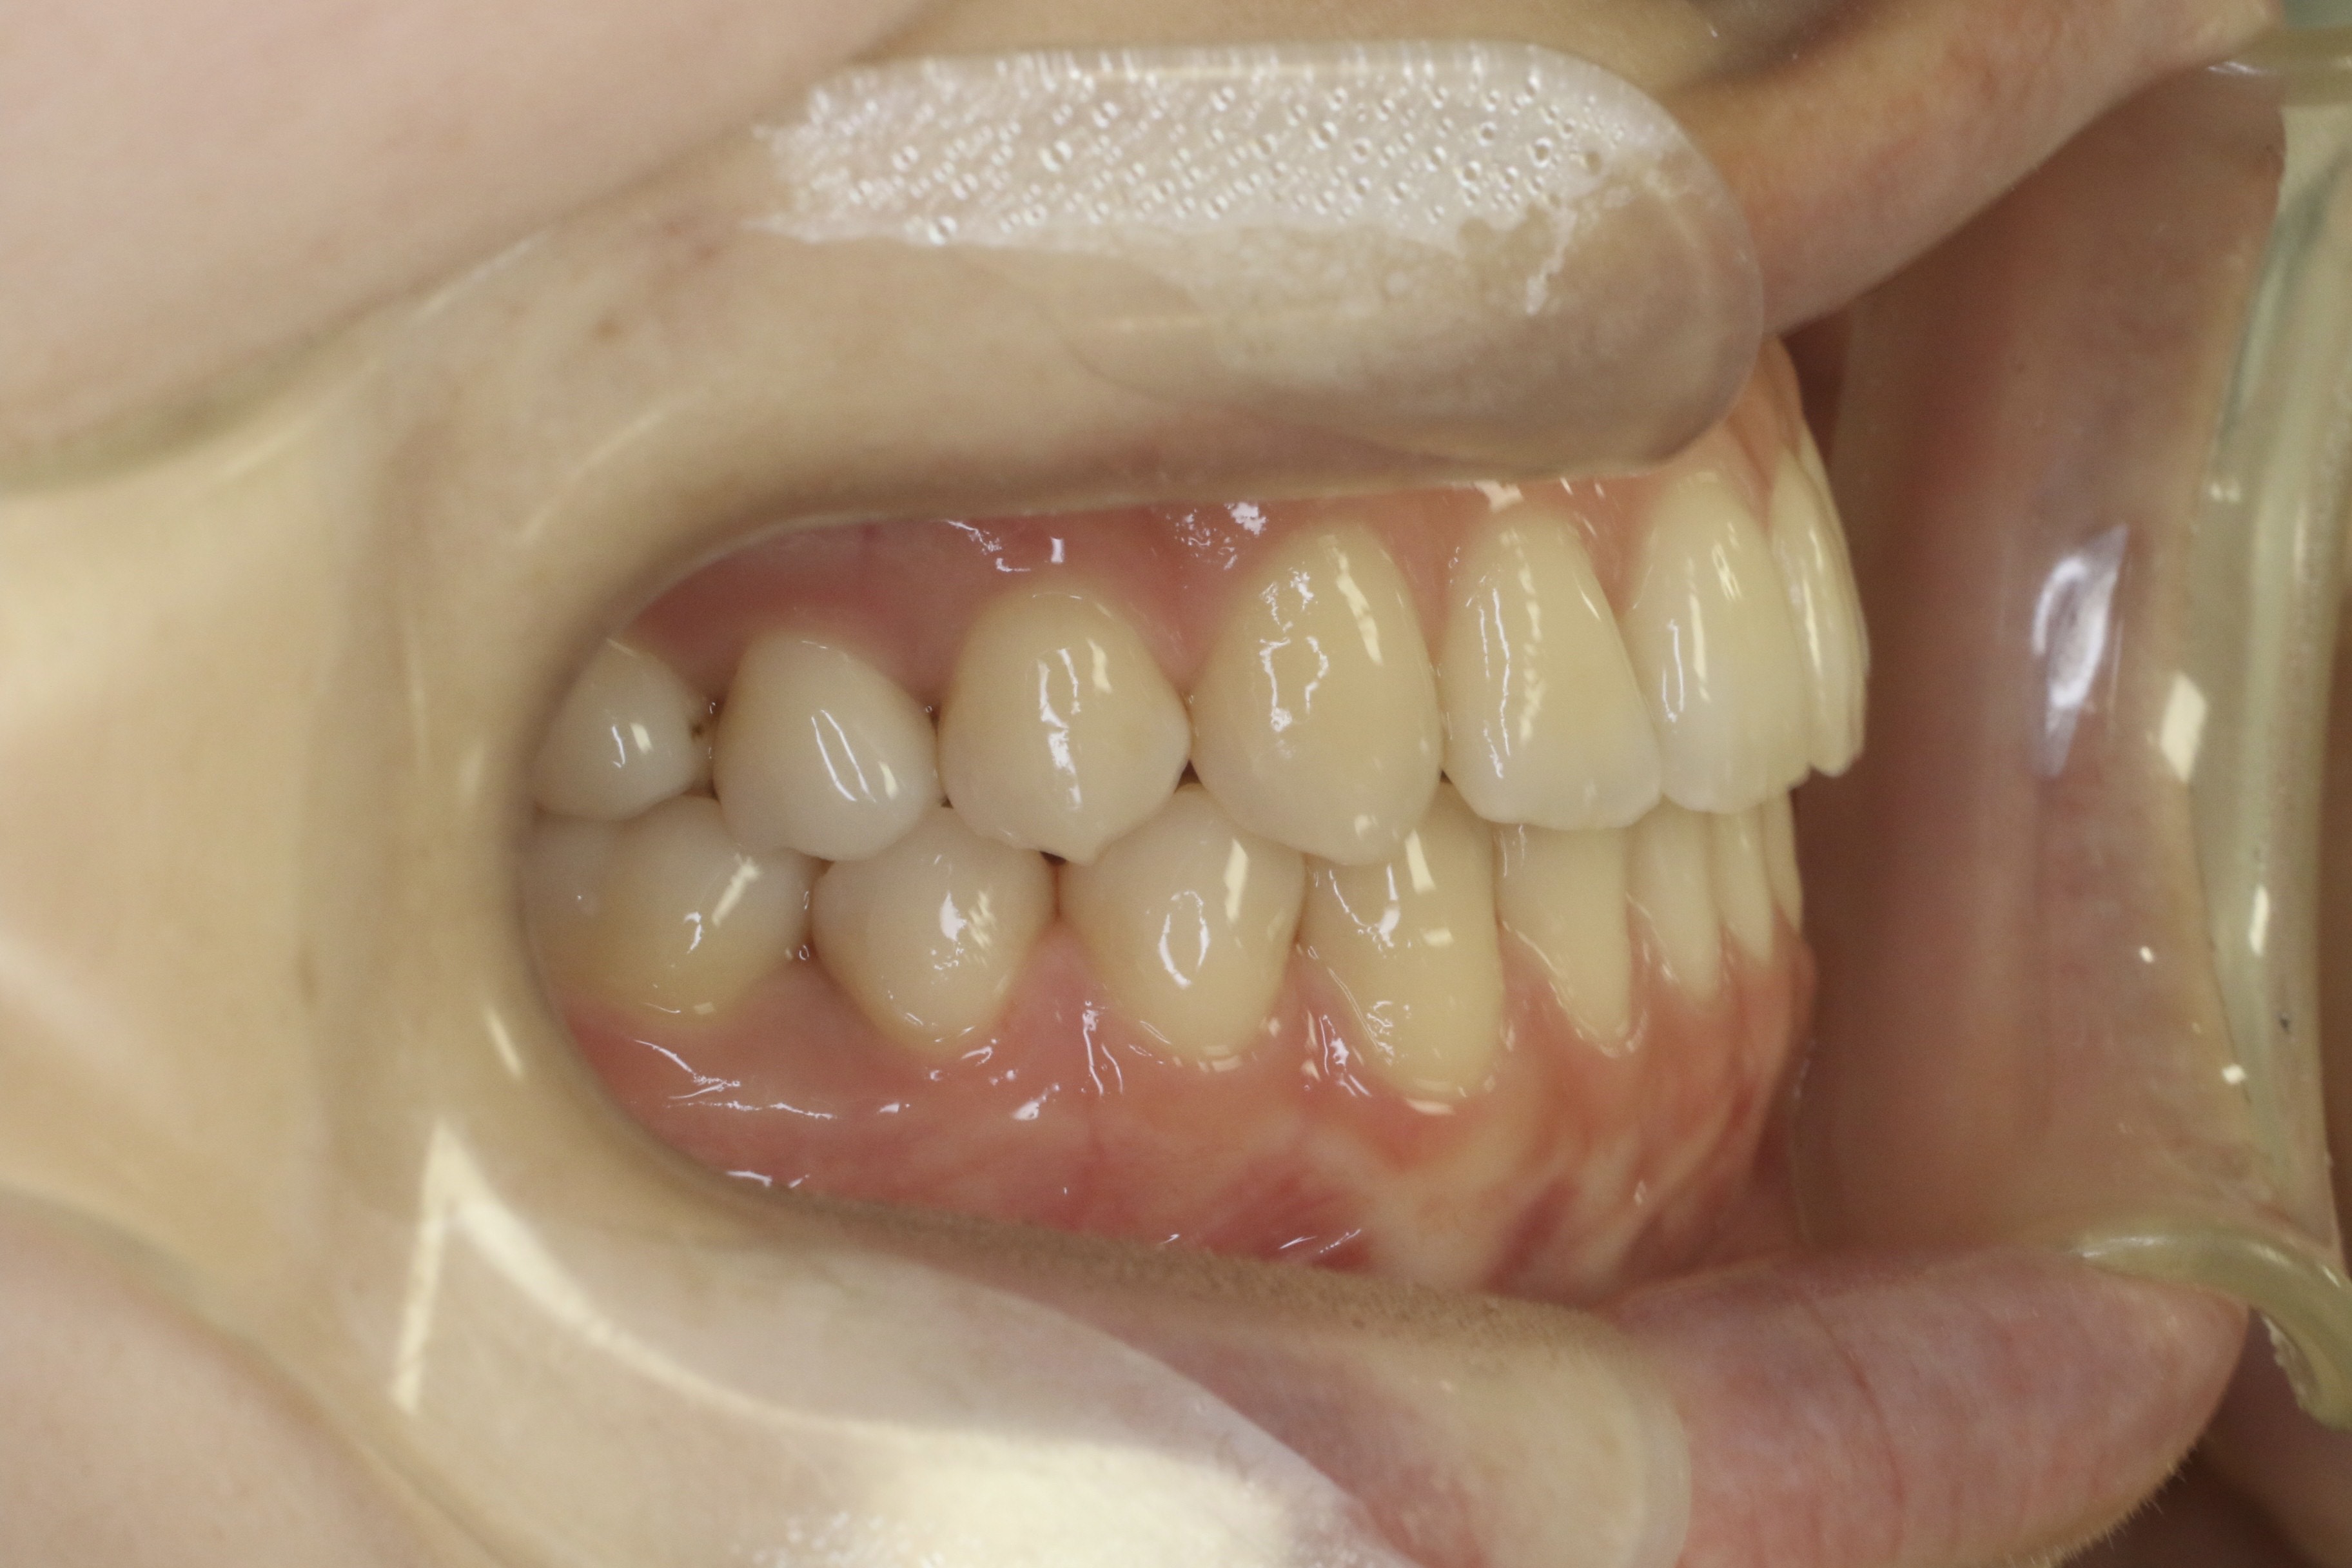

すきっ歯を治したい

年齢層 20代

性別 女性

主訴 【主訴】すきっ歯を治したい 【診断・症状】空隙歯列、1,1正中離開

治療費用 検査・診断:38,500-/裏側矯正治療:1,397,000-(※全て税込)

治療期間 約1年8か月(22回)

抜歯 無(非抜歯)

矯正の装置 裏側矯正(舌側矯正)

副作用、リスク 歯肉退縮,歯根吸収,疼痛,咬合の違和感,装置の違和感,虫歯,歯肉炎

case6_すきっ歯_before

Before

case6_すきっ歯_after

After